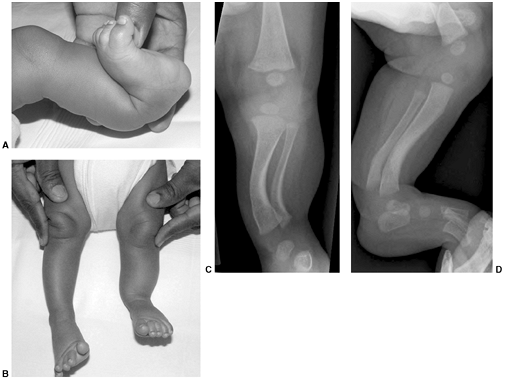

deformity characterized by equinus of the hindfoot and adduction of the

midfoot and forefoot with varus through the subtalar joint complex (Fig. 30.6). There is also a cavus deformity

![]() |

|

Figure 30.4 A, B:

Hindfoot position is measured as varus or valgus, on the basis of the angle subtended by the longitudinal axis of the tibia and the longitudinal axis of the hindfoot. C: With normal hindfoot mobility as the patient rises on the toes, the calcaneus tips into varus position. |

Figure 30.6 Clubfoot deformity is associated with forefoot supination, deep medial creases, and equinovarus of the hindfoot.